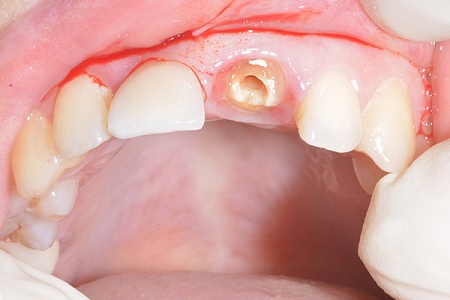

- Протезирование начинается с установки импланта на место удаленного зуба.

- После заживления устанавливается абатмент. Затем врач снимает слепки и отправляет их в зуботехническую лабораторию для изготовления протеза.

- Последний этап –– примерка, подгонка и фиксация постоянной коронки на имплант.

- При одномоментном протоколе имплантации все эти процедуры выполняются в течение одного приема.

Работы наших врачей